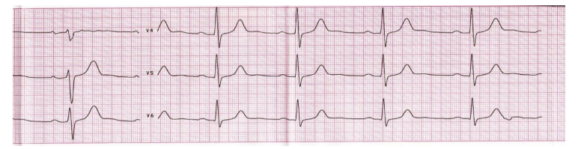

Сейчас вам предстоит встать на место кардиолога и понять, все ли в порядке с сердцем человека, который к вам обратился. С помощью специальной записи биения сердца можно определить, есть ли у человека какиелибо нарушения ритма. Рассмотрим пример кардиограммы человека (рисунок 13) и попытаемся определить его основные показатели.

Рисунок 13 – Кардиограмма

Для того чтобы что-либо рассчитать, недостаточно только рассмотреть изображение, если обратить внимание, то можно заметить, что поле поделено на клетки (контур клеток обведен толстой линией), а они, в свою очередь, еще на 25 клеток (тонкие прямые) (рисунок 14).

Рисунок 14 – Часть кардиограммы при увеличении

Все скачки и зубцы на графике означают сокращения сердца, их частоту можно посчитать по клеткам. Одна маленькая клетка на графике означает 0,02 секунды, большие клетки в длину составляют 5×0,02 секунды.

Рисунок 15 – Обозначения показателей кардиограммы

Нормальные показатели:

- частота сердечного ритма (интервал RR) у здорового человека находится в пределах от 60 до 100 ударов в минуту;

- интервал PR в норме составляет от 0,12 до 0,2 секунд;

- зубец Р показывает степень сокращений предсердий и в норме составляет менее 0,11 сек;

- комплекс QRS показывает степень сокращения мышечного слоя и в норме составляет менее 0,1 сек;

- QR-интервал показывает «перезарядку» сердца, когда мышцы расслабляются и готовятся к следующему удару, в норме составляет от 0,32 до 0,42 секунд.

Если какой-либо из показателей не будет соответствовать норме, это может значить какое-либо отклонение или заболевание человека.

Интервал RR отражает частоту сердцебиения, поэтому даже у здорового человека этот интервал может меняться, например, при сильном волнении пульс учащается, сильный шок замедляет пульс для экономии энергии на экстренный случай, и отклонение от нормы может сигнализировать о чем-то только при нарушении нескольких показателей.

В теле человека сокращение всех мышц происходит за счет отправки импульса из головного мозга, именно интервал PR показывает скорость передачи импульса для сокращения мышц сердца, если норма занижена, это значит, что сигнал передается быстрее обычного, и может быть следствием какой-либо патологии.

Зубец P показывает степень сокращения предсердий, то есть мышц, которые перекачивают кровь внутри сердца, уменьшение или увеличение может приводить к застою крови в сердце (при ослаблении) или недостаточному времени для транспортировки кислорода (при усилении).

Для определения любого заболевания необходимо сначала определить значения показателей на кардиограмме (рисунок 15). Все значения измеряются в секундах, напомним, что одна маленькая клетка (одно деление на схеме) отображает 0,02 секунды. Только частоту сердцебиения необходимо посчитать для 1 минуты.

Найдите значения следующих показателей и определите, в норме ли они:

- интервал RR – частоту сердечных сокращений (ЧСС);

- интервал PR;

- длину зубца Р;

- длину комплекса QRS;

- интервал QR.

Дайте заключение: в норме ли состояние сердца человека, исходя из его кардиограммы. Обратите внимание на то, изменяется ли интервал между зубцами R на всей кардиограмме (рисунок 12), нормально ли это?